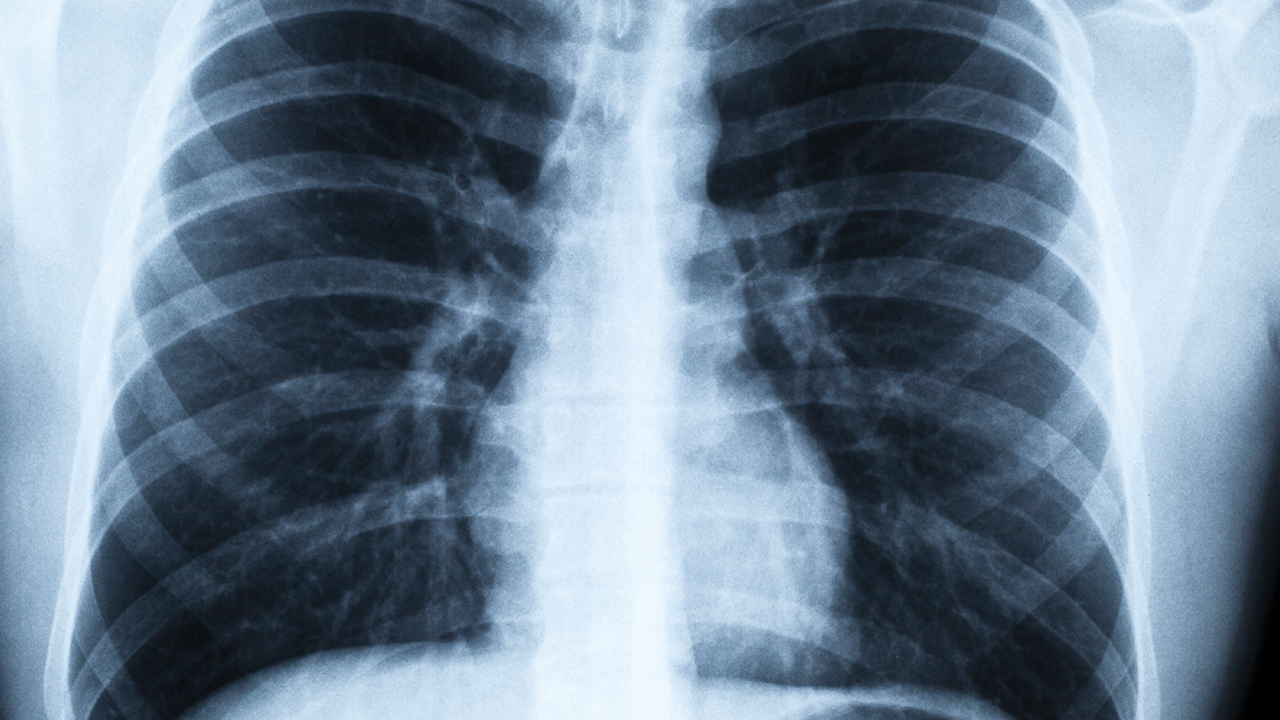

肺結(jié)核引起的胸痛多為隱痛或鈍痛,咳嗽或深呼吸時加重。胸痛可能與胸膜受累或肺部炎癥刺激有關?;颊呖蛇M行胸部X線或CT檢查明確病變范圍,治療以抗結(jié)核藥物為主,如乙胺丁醇片、鏈霉素注射液等。